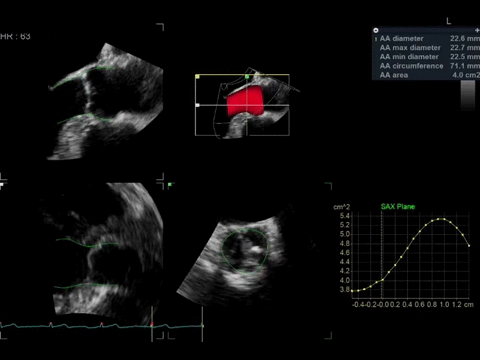

• Функция 4D Auto AVQ для автоматического выравнивания, сегментации и расчета размеров кольца аортального клапана, используемая при транскатетерной имплантации аортального клапана (TAVI)/транскатетерной замене аортального клапана (TAVR).

• Многосрезовая визуализация в реальном времени или в режиме воспроизведения, позволяющая использовать массивы 4D данных для получения стандартных проекций по длинной и короткой оси.

• Лазерные линии, улучшающие восприятие глубины и показывающие взаимосвязь объемных 4D изображений и двумерных срезов.